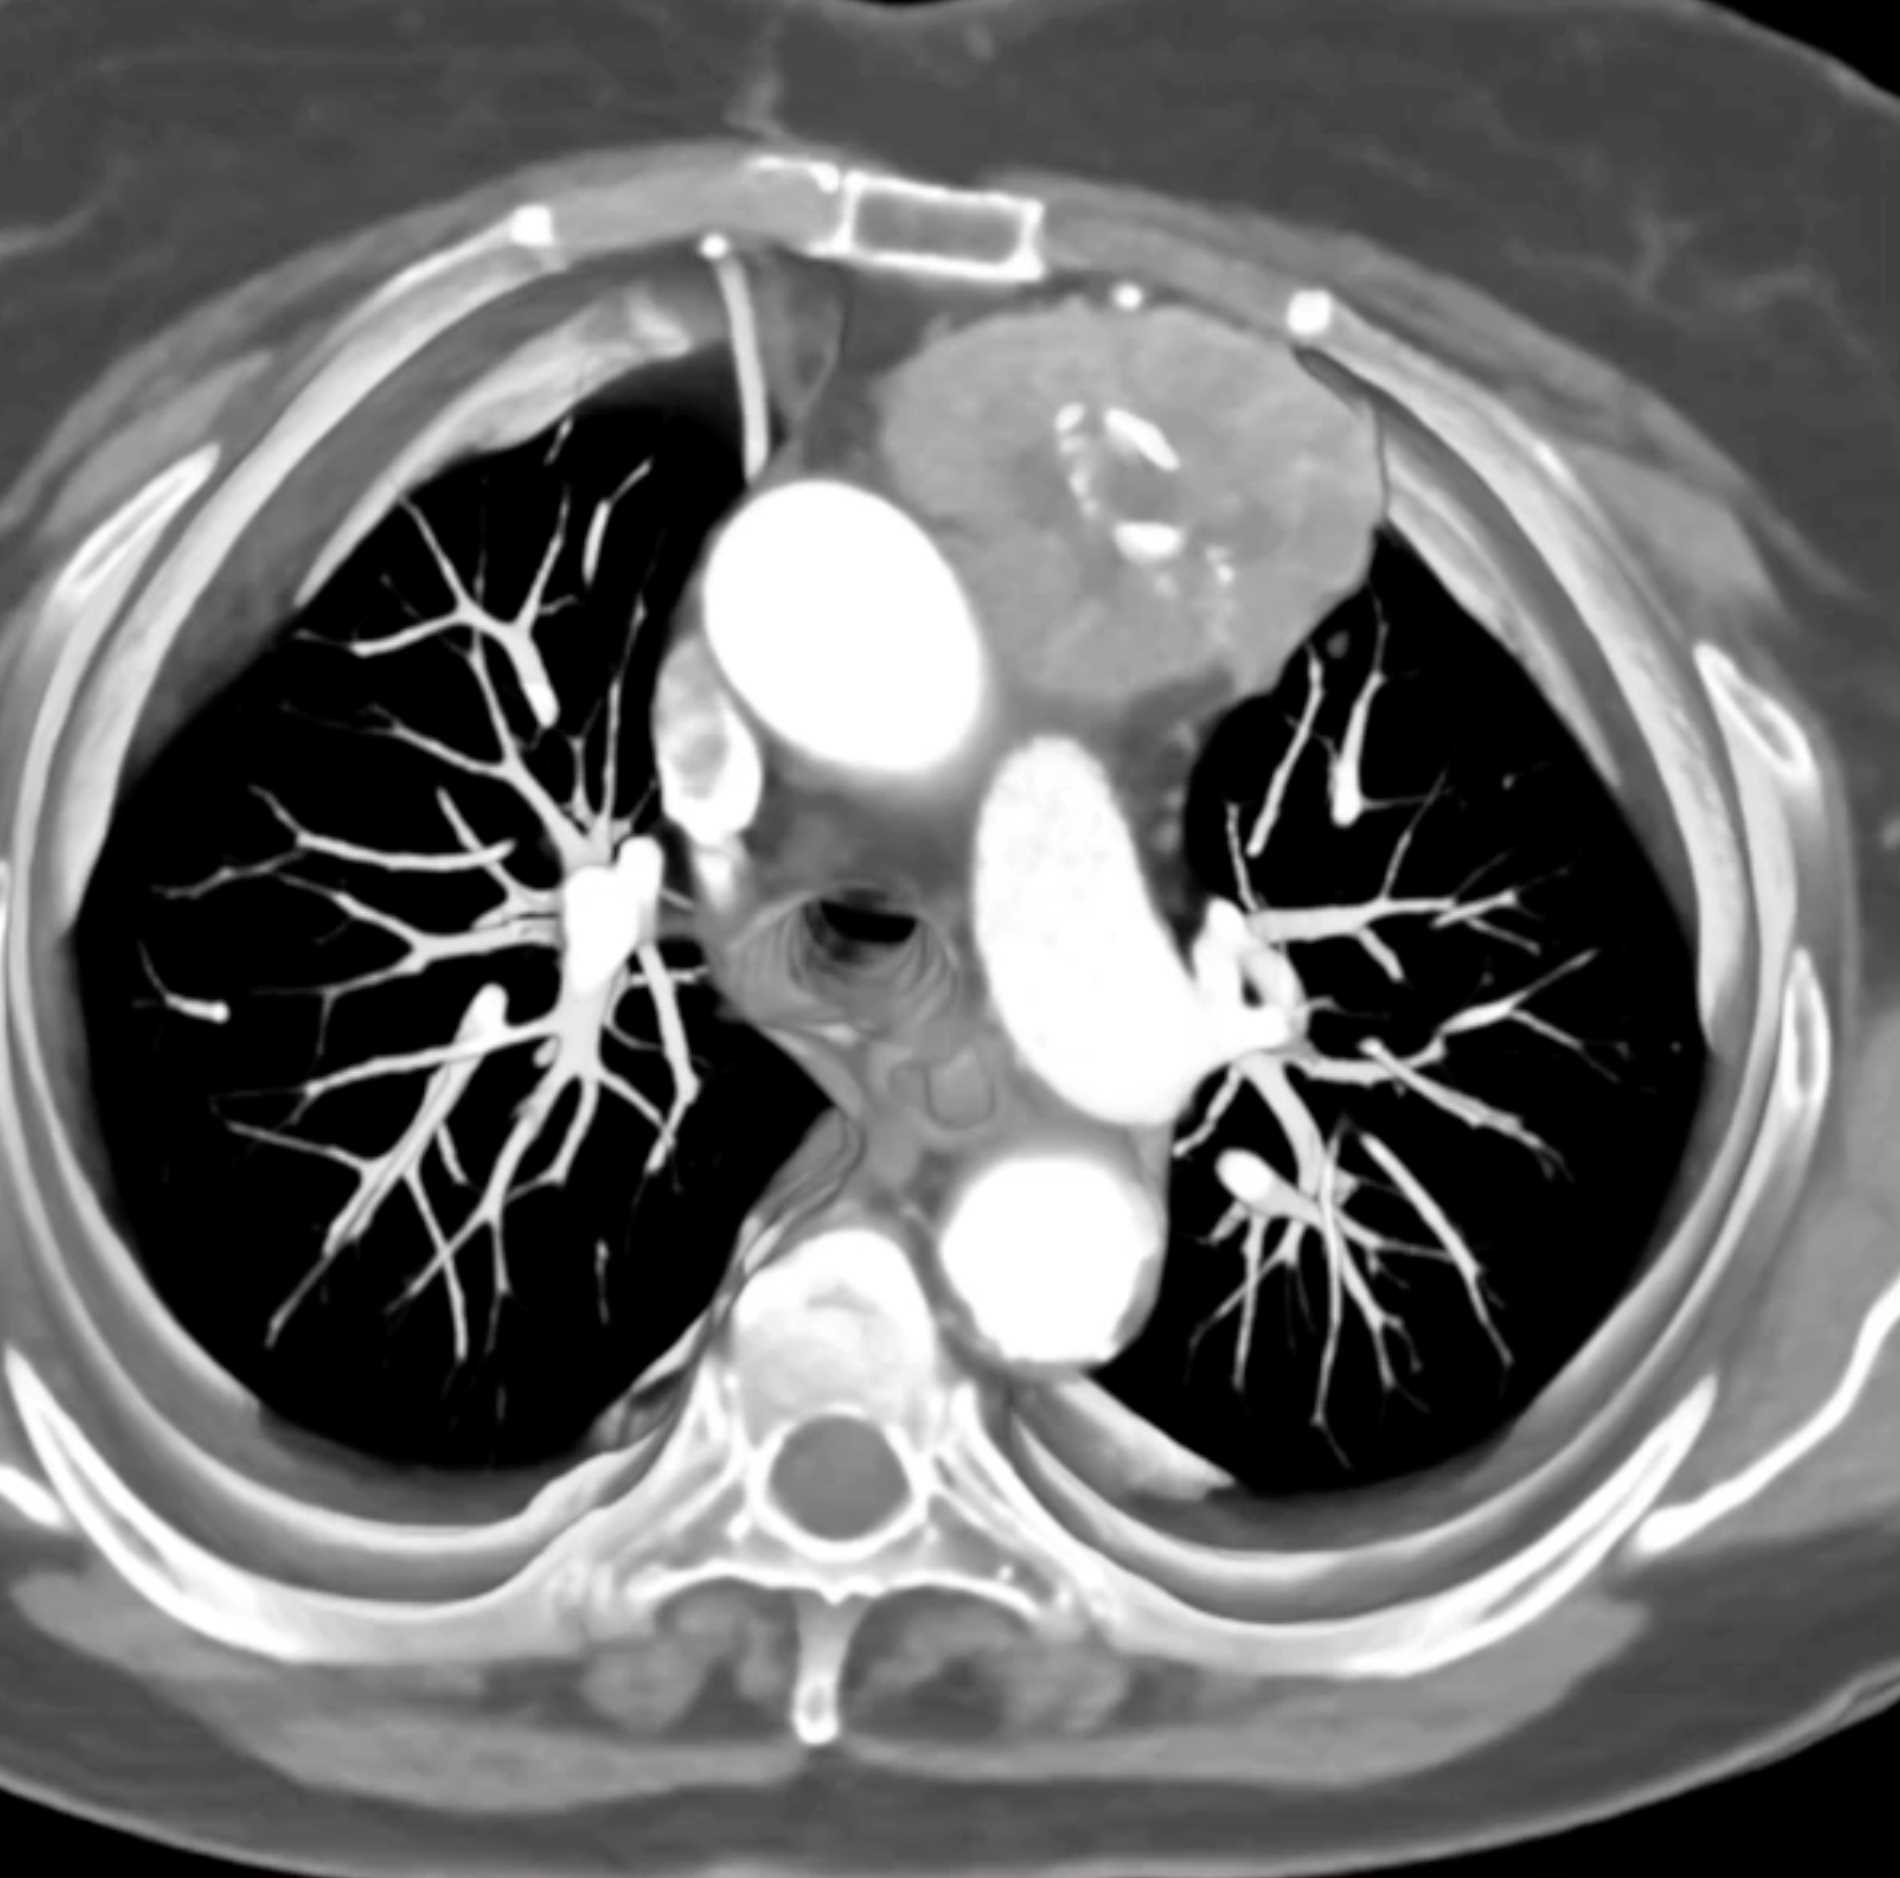

Thymic Carcinoma